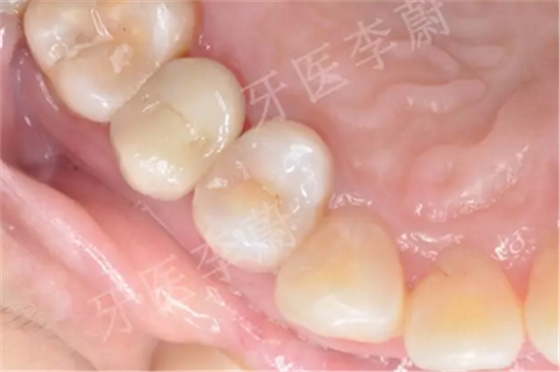

15牙二氧化鋯烤瓷冠舌面觀

15牙二氧化鋯烤瓷冠頰面觀

15牙戴入二氧化鋯烤瓷冠